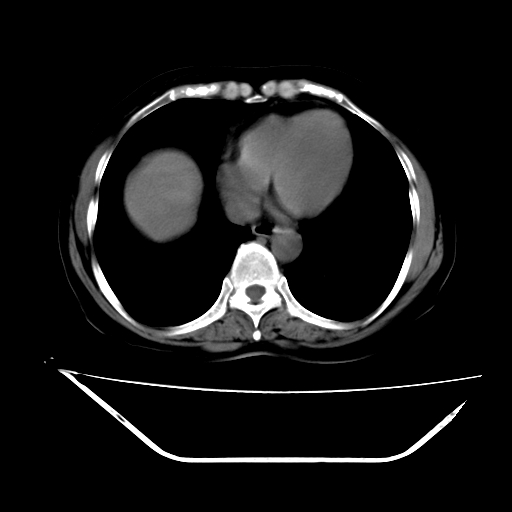

ct增强

考虑肝腺瘤出血可能,肝血管瘤增强表现不是很典型,放在第二。

6月份ct片显示肝内巨大混杂密度团块,伴包膜下积液(内含液液平面),增强多无明显强化。只能考虑肝占位病变,并肝内、血膜下血肿。肝ca并出血多见,而肝血管瘤并破裂出血少见。

从平扫+增强及治疗后复查片,病变明显缩小,不考虑肝癌出血可能,还是考虑为良性病变可能性大;单纯血肿并包膜下积液吧,病变强化没法解释,肝血管破裂出血吧,增强不符合典型血管瘤的表现,良性肿瘤破裂出血吧,复查片看来好像也不太支持(没做强化也不太好说)。本人还是考虑单纯肝内血肿并包膜下积液,强化是不是血管有外渗。